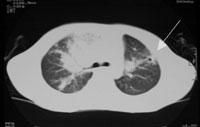

胸部CT(1):入院7天(病程67天) 胸部CT(2):入院7天(病程67天) (双肺多发点片状高密度影,右下肺背段可见致密团块影,外缘贴近胸壁,左上中肺内见一圆形病灶,中空,双肺门影增浓,心影增大,左室为主,纵隔内未见肿大淋巴结影)

任甄华 主治医师(放射科):X线胸片对于提示肺栓塞有重要参考价值,单纯肺栓塞胸片可能有五种表现:(1)缺血性改变:局部血管纹理减少,即Westermark征;(2)肺血管大小的改变;(3)心脏变化;(4)肺体积缩小;(5)胸膜渗出。值得强调的是,感染性心内膜炎引起的肺栓塞影像学改变与其他病因引起者不同,典型表现为散在、双侧的外周结节与不同程度的肺空洞性损害,损害呈圆形或楔形,多发生在下肺的外侧部分。本病例就体现了这一特点(见附图),这可能与栓子较小且携带病原菌,造成栓塞部位的继发感染有关。

但必须指出,肺栓塞的X线胸片表现多种多样,呈典型锥形改变的非常少见,部分肺栓塞的胸片可看不见任何异常表现。相当一部分胸片呈肺浸润表现,与肺炎相似。可从以下两点加以区别:①肺部一侧病变吸收,而另一侧出现新阴影的多发病变;②片影吸收呈“溶化征”,而肺炎吸收中片影出现密度不均现象,由此可见,在诊断中胸片的动态观察更为重要。有以上表现者应高度怀疑肺栓塞,再结合患儿是否存在高危因素,临床可做出正确诊断。切勿仅凭胸片轻易排除肺栓塞。本例患儿存在感染性心内膜炎、三尖瓣赘生物的基础病变,2个月病程中肺部阴影变化了3次,每次均为原有病灶吸收,在不同部位又出现了新的浸润影,结合临床表现,肺栓塞可确诊。